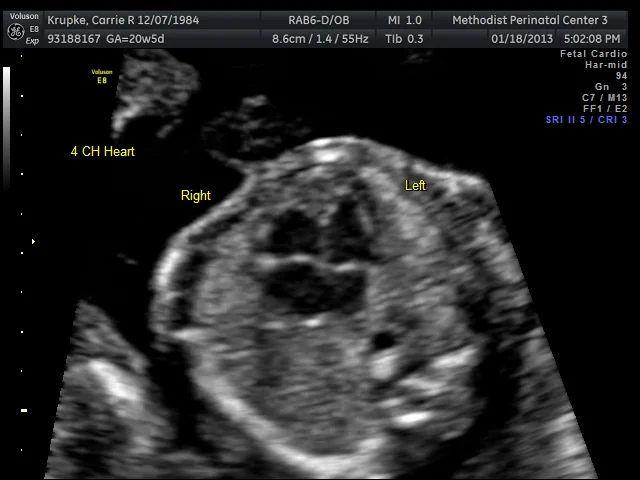

A great profile, but boy, did Baby make the tech work hard from there on out! In true Williams style, Baby was working on it’s flip turns the entire time I was on the table. Which, originally, should’ve been 45 minutes, but ended up being a whopping 75! Think of it as the best 75 minute TV show you’ve ever watched. And yes, that includes Downton Abby. 😉 Our first tech was a student who was weeks away from graduating and the full-time tech was watching the print-outs from another room. The student’s first comment was how beautiful Baby’s heart was. (And that was when mine melted.)

The full-time tech came in shortly afterwards and also commented how beautiful Baby’s heart was. She proceeded to go for shots of the spine and other appendages. Intermittently, she’d go looking to see if Baby was a He or She. Baby’s flip turn form was stellar the entire time, with its legs closed and feet above the head. (In true “Gerard flexibility” fashion as well.) So the tech would go from searching to measuring another body part. Rinse-repeat. Rinse-repeat.